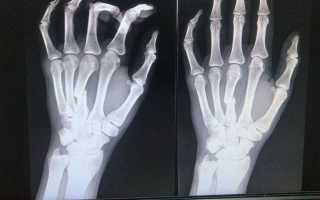

Диагностика перелома кисти руки обычно включает физический осмотр врача, который оценивает симптомы и проводит тесты на подвижность. Для подтверждения диагноза могут быть назначены рентгенографические исследования, которые помогут визуализировать поврежденные кости.

По истечении 4 недель гипсовой иммобилизации обязательно проводится повторная рентгенография для оценки процесса заживления. В случае неправильного сращения костей может потребоваться повторная репозиция.

Еще одним серьезным осложнением является асептический некроз, который возникает из-за недостаточного кровообращения и приводит к омертвению костной ткани. Именно поэтому контрольные рентгеновские снимки имеют такое большое значение — они позволяют своевременно выявить участки, где ткани не восстанавливаются.